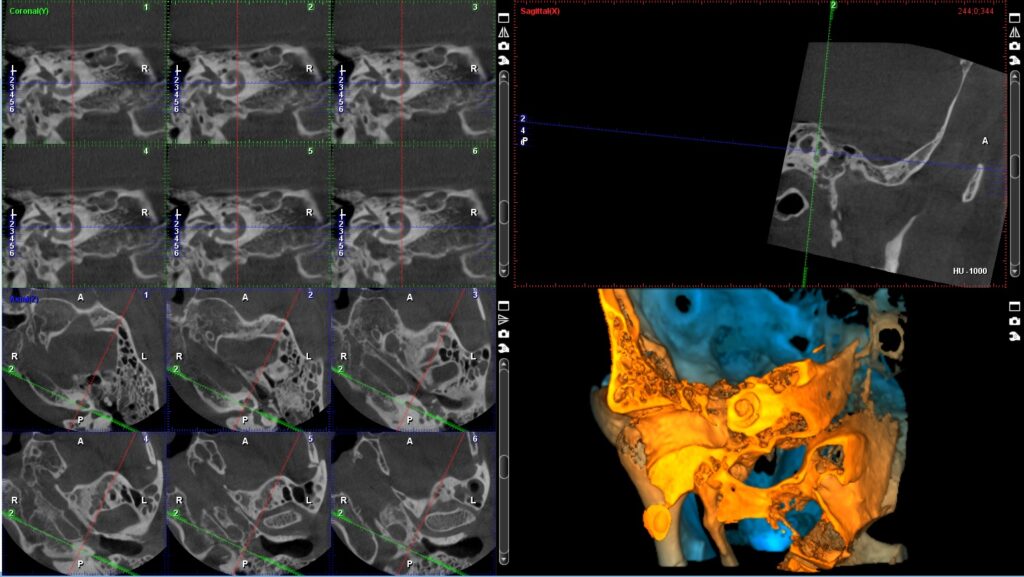

Programi za sinus, TMZ, cefalolometriju